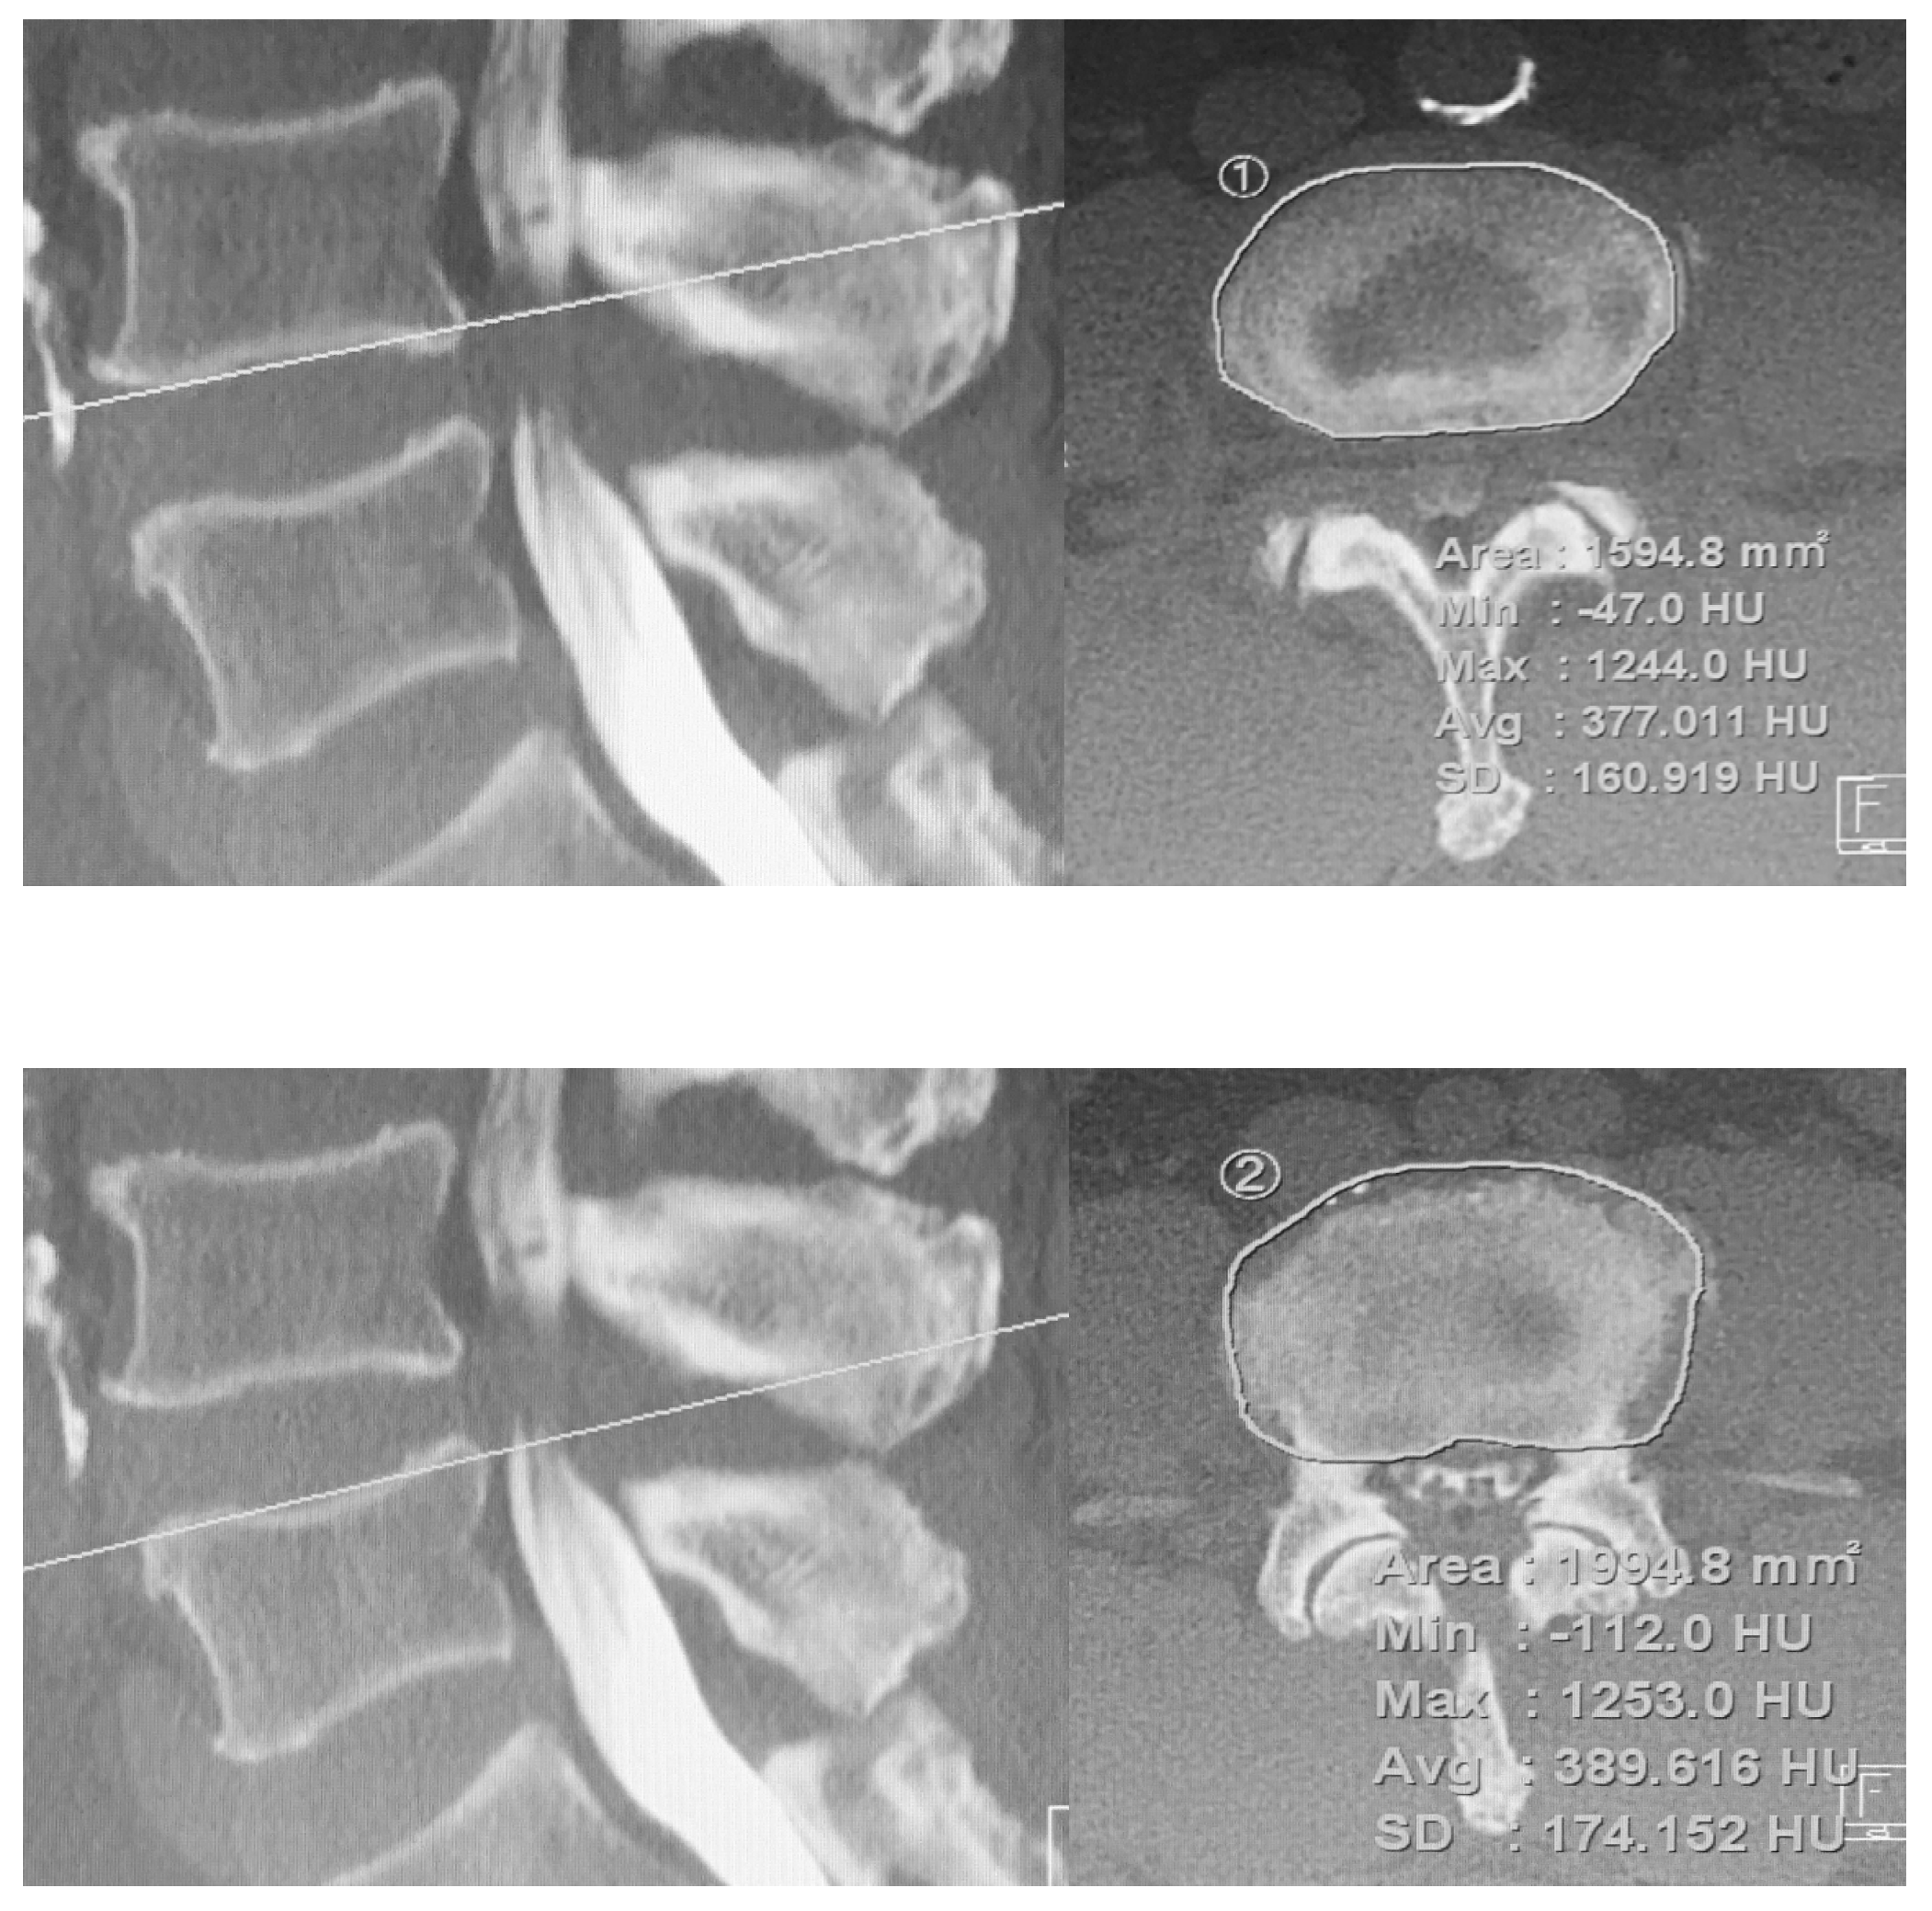

2.3. Radiological Assessment

- Kim, K.J.; Kim, D.H.; Lee, J.I.; Choi, B.K.; Han, I.H.; Nam, K.H. Hounsfield Units on Lumbar Computed Tomography for Predicting Regional Bone Mineral Density. Open Med. 2019, 14, 545–551. [Google Scholar] [CrossRef]

- Schreiber, J.J.; Anderson, P.A.; Hsu, W.K. Use of computed tomography for assessing bone mineral density. Neurosurg. Focus 2014, 37, E4. [Google Scholar] [CrossRef]

- Zaidi, Q.; Danisa, O.A.; Cheng, W. Measurement Techniques and Utility of Hounsfield Unit Values for Assessment of Bone Quality Prior to Spinal Instrumentation: A Review of Current Literature. Spine 2019, 44, E239–E244. [Google Scholar] [CrossRef]

- Xi, Z.; Mummaneni, P.V.; Wang, M.; Ruan, H.; Burch, S.; Deviren, V.; Clark, A.J.; Berven, S.H.; Chou, D. The association between lower Hounsfield units on computed tomography and cage subsidence after lateral lumbar interbody fusion. Neurosurg. Focus 2020, 49, E8. [Google Scholar] [CrossRef]

- Zhou, J.; Yuan, C.; Liu, C.; Zhou, L.; Wang, J. Hounsfield unit value on CT as a predictor of cage subsidence following stand-alone oblique lumbar interbody fusion for the treatment of degenerative lumbar diseases. BMC Musculoskelet. Disord. 2021, 22, 960. [Google Scholar] [CrossRef] [PubMed]

| Cranial endplate Hounsfield unit (HU) | 325.0 (68.4) | 281.2 (55.2) | 0.016 * | |

| Caudal endplate Hounsfield unit (HU) | 293.5 (69.6) | 245.4 (62.8) | 0.012 * | |

| Mean endplate Hounsfield unit (HU) | 310.2 (56.5) | 263.3 (54.0) | 0.004 * | |